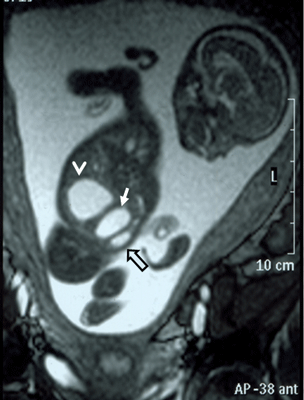

In the axial plane, besides type IV SCT (big arrow head) and hydrometrocolpos (white arrow); both kidneys (white asterix) appeared in normal loca¬tion and anatomy (Fig. 4). In the coronal plane fetal bladder (black empty arrow) was noticed (Fig. 5).

Figure 4: Fetal MRI axial plane. |